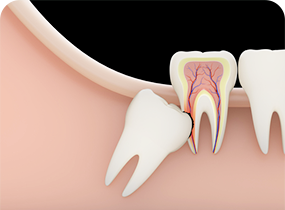

CASE 03

사랑니가 어금니 뿌리를

망가뜨리는 경우 -